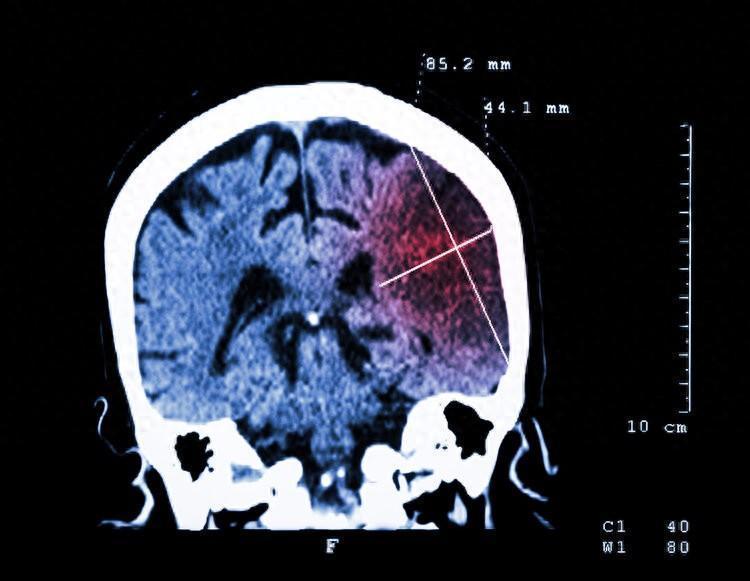

河北省張家口市宣鋼醫院神經內科主治醫師王莉指出:腦梗又被稱爲缺血性腦卒中,是指大腦血管受多種病因所致出現堵塞,引發了腦部血液供應障礙,導致部分腦組織缺血、缺氧壞死,甚至出現了相應神經功能缺損的症狀。

首都醫科大學宣武醫院趙文博提醒:平常要注意檢查,判斷腦血管狹窄常用CT血管造影檢查、頸部和腦部血管超聲檢查以及磁共振血管造影檢查三種方法。